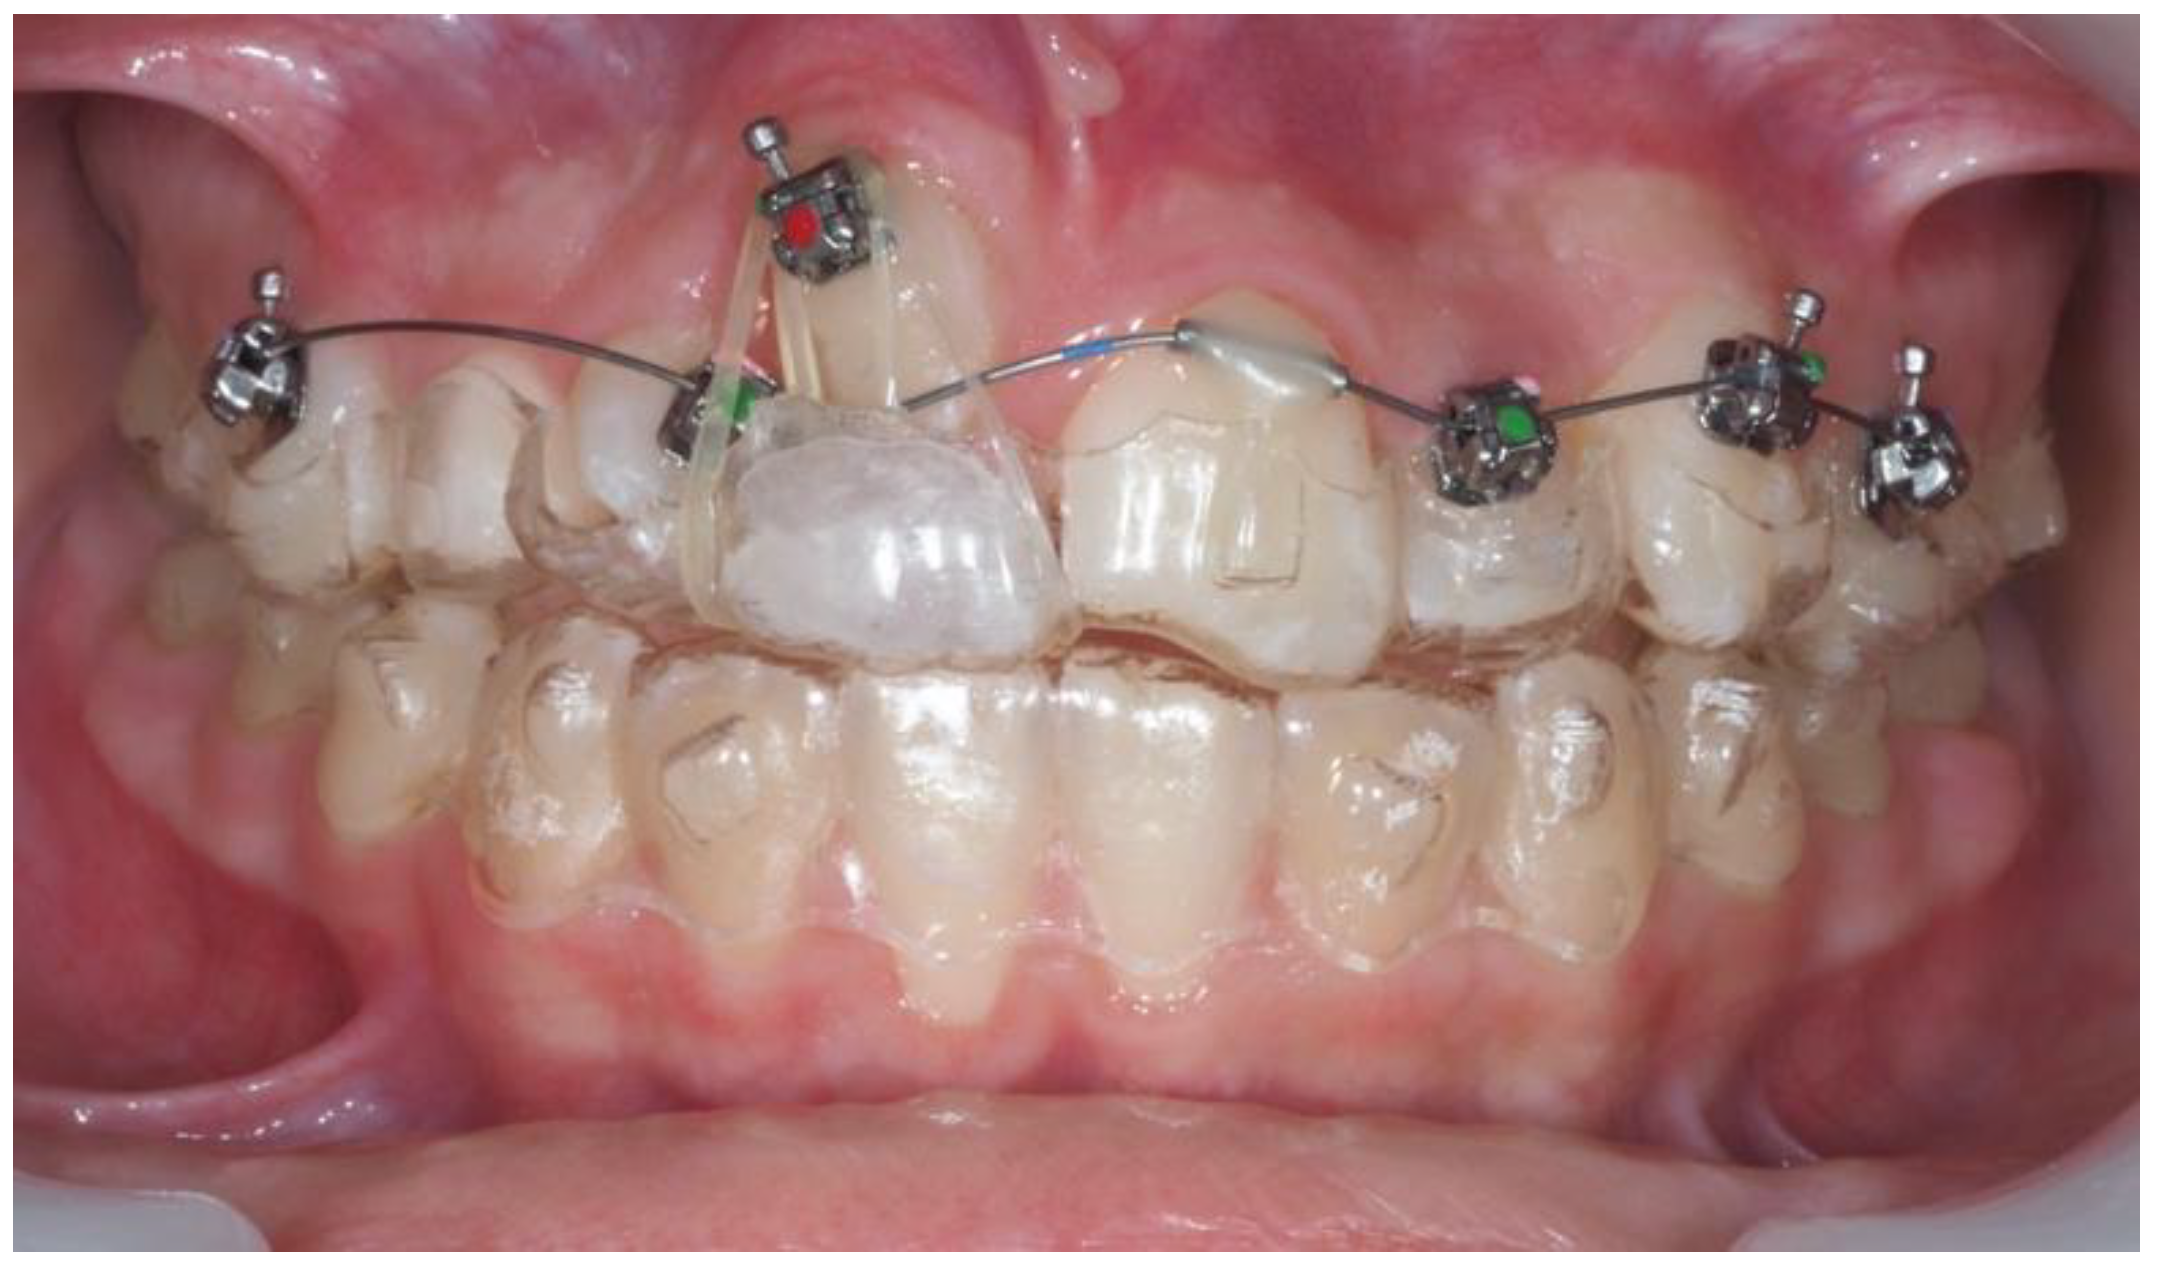

| Pinho T., Amaral R. 2025 | ♀ 13 YO | Mx.C.I1 | C | R | V (impacted) | Cl I | Maintained | -Total root resorption of tooth #11 due to the position of the ectopic canine |

3.2. Clinical Case